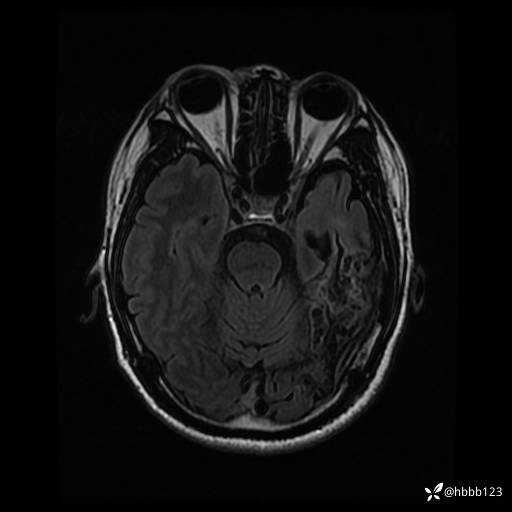

患者男,43岁。

简要病史:癫痫患者复诊,昨日发作5-6次,建议住院进一步治疗。

入院完善脑癫痫组合序列:

DWI: